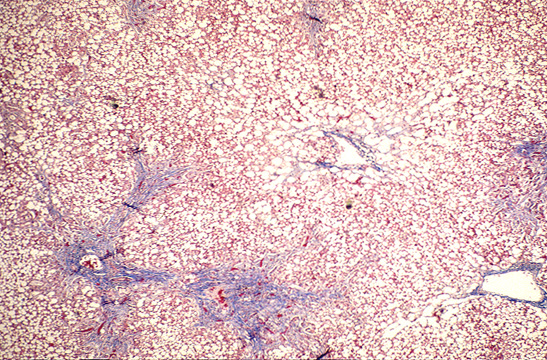

untitled [www.meddean.luc.edu] untitled [www.meddean.luc.edu] From meddean.luc.edu

untitled [www.meddean.luc.edu] Source: meddean.luc.edu